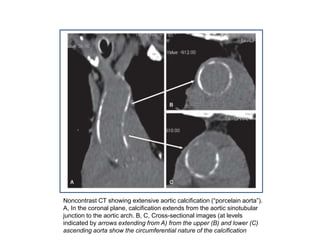

Noncontrast CT showing extensive aortic calcification (“porcelain aorta”).

A, In the coronal plane, calcification extends from the aortic sinotubular

junction to the aortic arch. B, C, Cross-sectional images (at levels

indicated by arrows extending from A) from the upper (B) and lower (C)

ascending aorta show the circumferential nature of the calcification

Noncontrast CT showingextensive aortic calcification (“porcelain aorta”). A, In the coronal plane, calcification extends from the aortic sinotubular junction to the aortic arch. B, C, Cross-sectional images (at levels indicated by arrows extending from A) from the upper (B) and lower (C) ascending aorta show the circumferential nature of the calcification